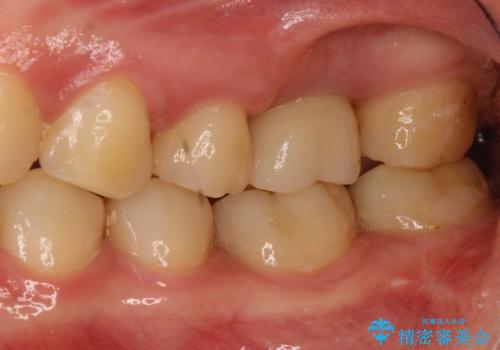

奥歯が割れてしまった! → インプラントによるかみ合わせの回復

→2時手術の後、インプラントレベルの型どりにて上部構造まで完成させる

インプラントの種類:Zimmer spline

かぶせものの種類:Bellezza